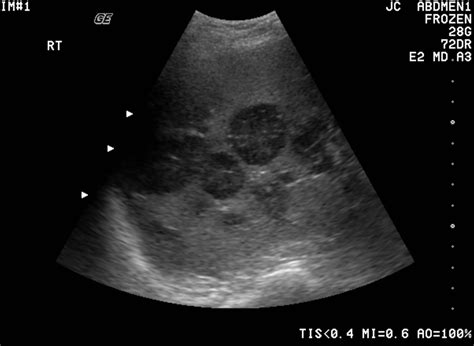

• Tumor Detection: Sonography can identify tumors and other masses that may indicate the presence of cancer. By examining the size, shape, and borders of these masses, healthcare providers can determine whether further investigation is necessary.

• Liver Cancer: Liver sonography can detect tumors and other abnormalities that may suggest liver cancer.

• Texture and Echo Pattern: The texture and echo pattern of the tissues are analyzed to determine if they are benign or malignant.

• Blood Flow: Doppler sonography may be used to assess blood flow within the tissues, which can provide additional information about the nature of the abnormality.

• Doppler Sonography: This technique uses Doppler effect to assess blood flow within tissues, helping to differentiate between benign and malignant masses.